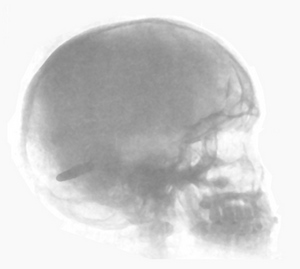

Even the brain is not a dead certainty (excuse the pun). Photo below is an X-ray, taken thirteen years after he was shot, of a troopersÂ’ head (Co D, 1st Neb Vol infantry), clearly showing the 7mm caliber bullet lodged in the back of his brain. The bullet entered his head just off centre above the left eye, although it caused him some inconvenience, the only medical treatment he received was a sterile wound dressing. La Garde cites other instances supported with photographs and X-rays, while more recently there was a well documented case of a journalist covering a dockyard strike who was knocked unconscious in a scuffle. He thought it was the brick that he saw lying next to him when he came round, but some years later when he went for a check up on eye trouble they found the .45 bullet in his brain. Certainly the frontal lobes are not vital to life, as the old system of 'frontal lobotomy' for criminals shows. It is only the back third of the brain which is essential for life support functions. I wonder how many of the elephants that have regained consciousness after a brain shot and wondered off actually had bullets through the brain. 'Pondoro' Taylor always reckoned that it was concussion from a near miss that knocked the animal unconscious, but I wonder... Whatever the reality, it simply reinforces the contention that any animal that falls to a brain shot must be assumed to be only concussed and a heart shot put in to be sure...to be very sure.

Skull Xray

Taken from page 174 Gunshot Injuries by La Garde.